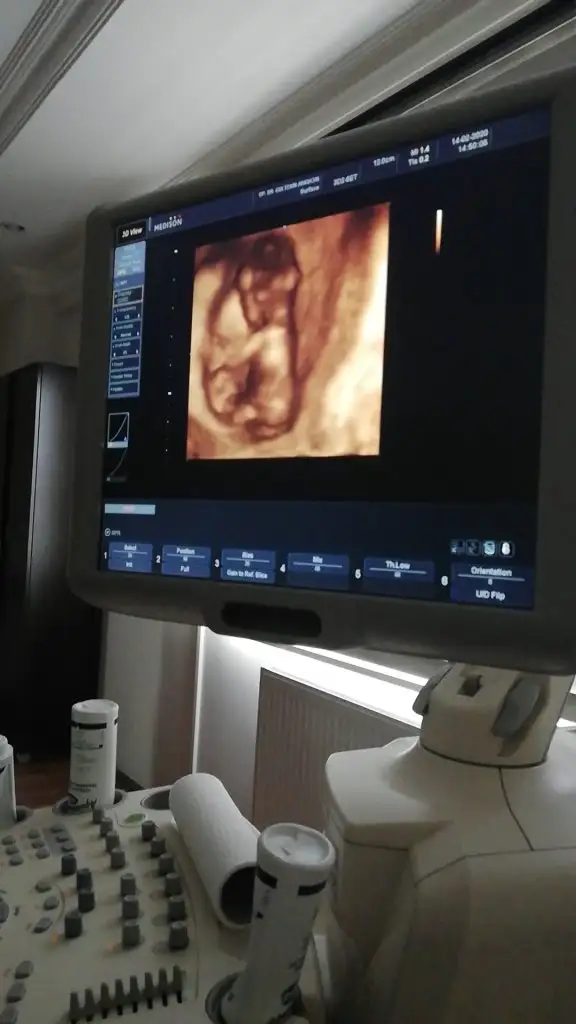

dr soylemeden siz gorun genital nub teorisi ( bebegin cinsiyeti)

Merhabalar Tahmin yorumlarınızı heyecanla takip ediyorum. Bende sabırla 12. haftamızın dolmasını bekledim. Bir yorumda benim için yaparmısınız Buğün 12+1 olduk.